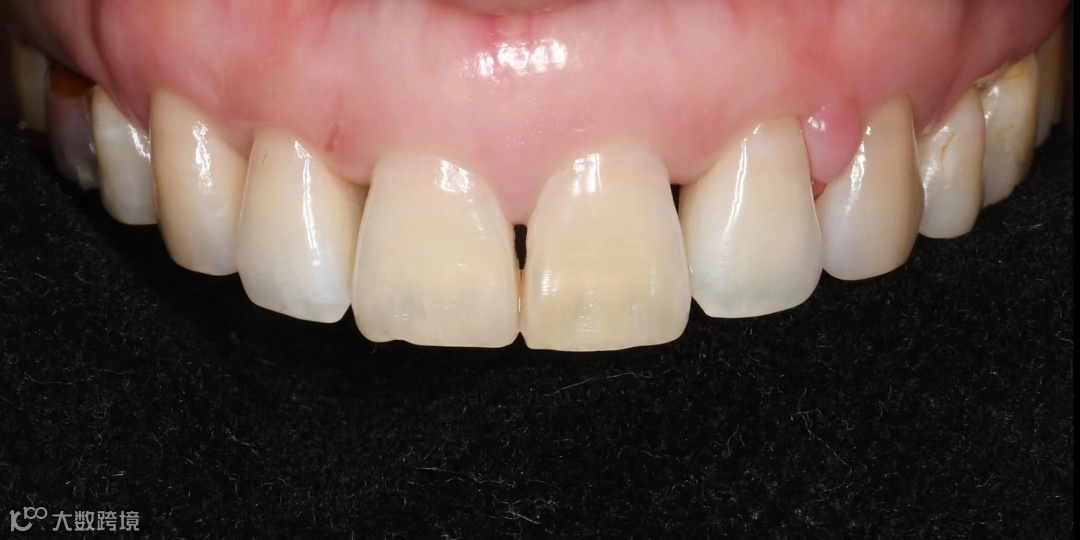

贴面美容性修复前:

贴面美容性修复后: